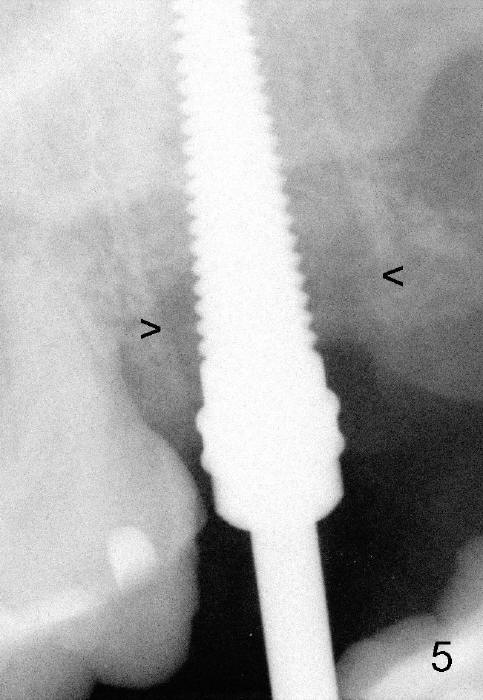

A 57-year-old lady presents for abscess buccal to the tooth #15 (Fig.1 A). Mesial and distal to the occlusal composite (Fig.2 C) is a crack line. In addition to long furcated roots, the upper border of the bone is not shown in this preop PA (arrow). Fig.3 is taken to show a thin septum surrounded by the mesiobuccal (MB), distobuccal (DB) and palatal (P) sockets (Fig.3). Osteotomy is initiated in the septum by 1.2 and 1.5 mm pilot drills, followed by 2,3,4 mm rounded tapered osteotomy at the depth of 17 mm. Nose blowing test is carried out after each step with negative result. Stability is achieved when a 4.5 mm tap is inserted at 17 mm, but the upper end of the tap is not visible (Fig.4,5). When a 5 mm tap is placed, stability is decreased, probably because the coronal end of the septum starts to break down (due to expansion). To re-gain stability, the 5 mm tap needs to go deeper. A 6 mm tap also achieves satisfactory stability at 20 mm. When the tap is removed, there is no air leakage. A 6x20 mm implant is placed with insertion torque > 60 Ncm; the upper end of the implant is still out of view in PA (Fig.6). Another problem is that the implant needs to go deeper to obtain sufficient occlusal clearance. The lower first molars and the 2nd premolars are missing. A panoramic X-ray has to be taken to show the apical end of the implant: ~ 3 mm into the sinus (Fig.7 ^). The maxillary tuberosity appears to grow downward (arrow). In other word, the tooth #15 appears to have been intruded due to overloading.